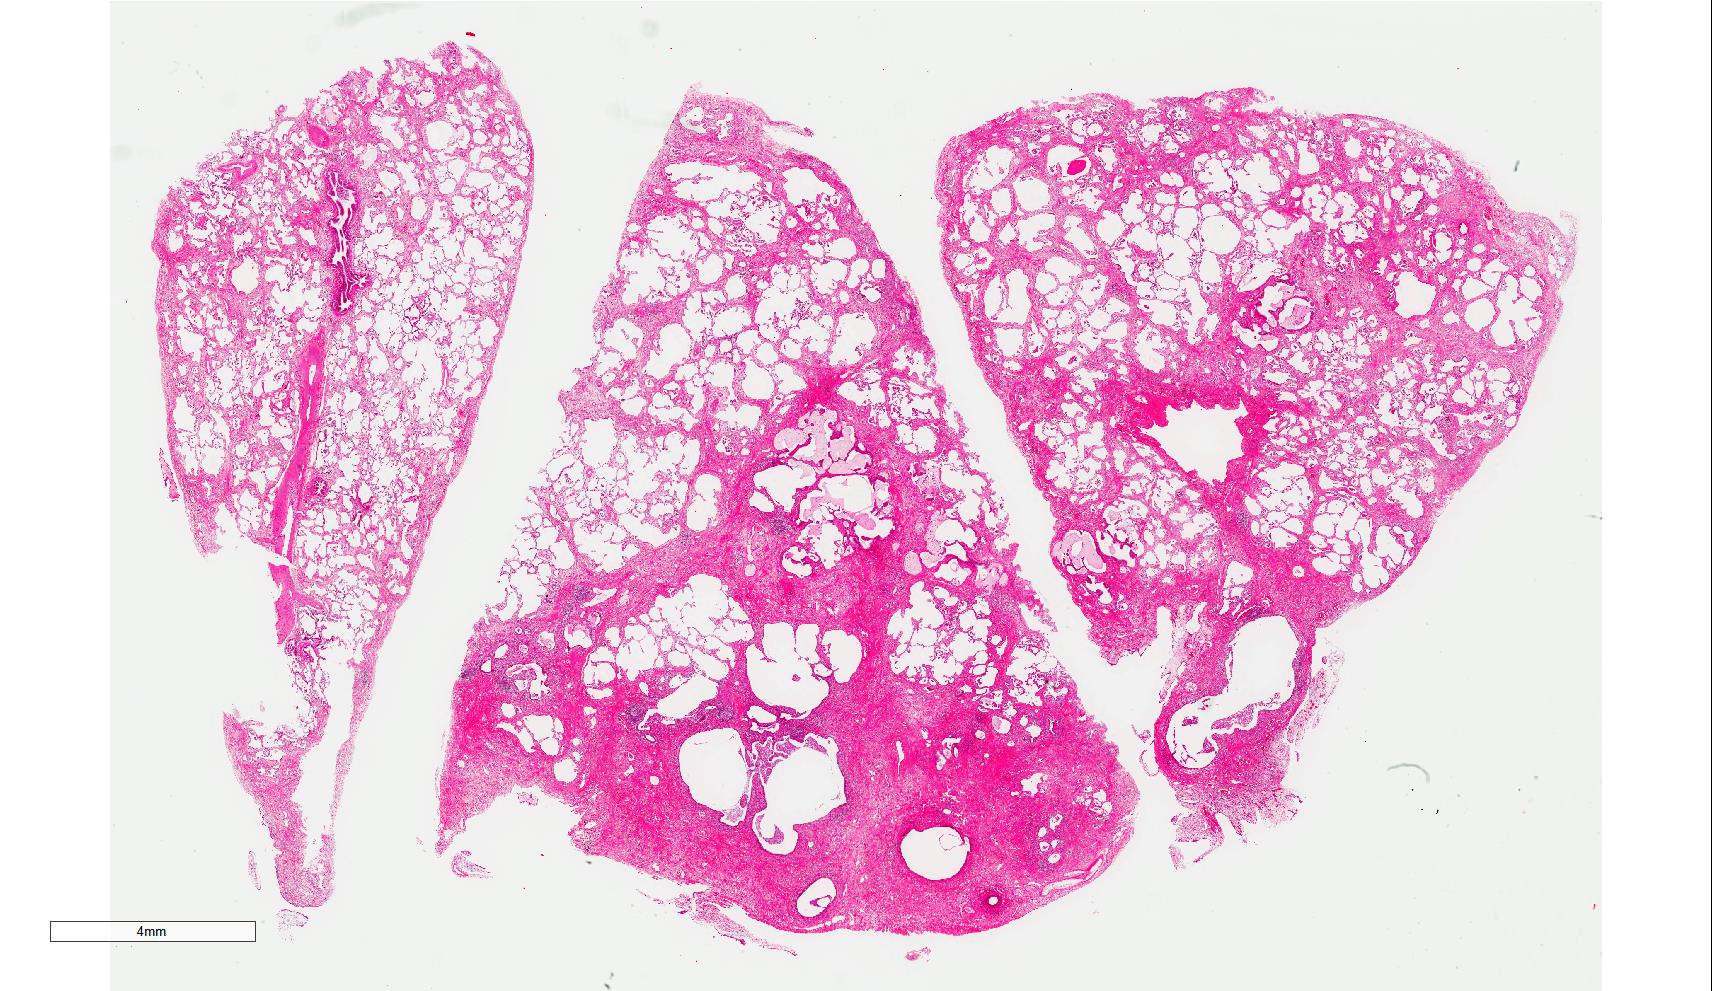

Gross description

- Diffuse involvement with mild to moderate increase in lung weight

- Fibrotic changes in lower lobes

- Homogeneous and diffuse compared to UIP

- Shrunken lung

- Traction bronchiectasis can be seen

- Honeycomb change can be seen but limited

Microscopic (histologic) images

Scroll to see all images.

Contributed by Akira Yoshikawa, M.D.